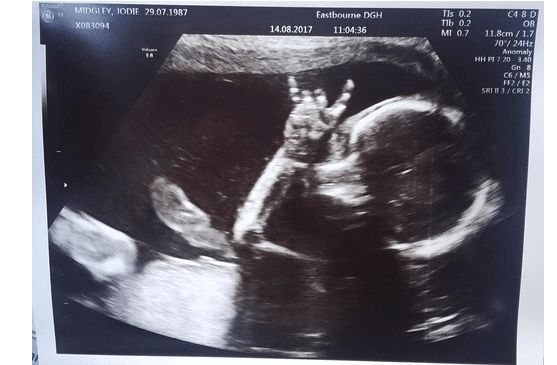

Tak takýto snímok matkinho tehotenského brucha ste ešte zrejme nevideli. Doktor jej urobil ultrazvukový snímok, no takýto ste ešte nevideli. Jodie Lee a jej partner Davie Langham sa s láskou pozerali na svoju dcéru počas ultrazvuku, keď odrazu zbadali prekvapivé gesto, ktoré urobila ich malá dcérka.

Milovníci hudby počúvali chytľavú pesničku od Motown, keď dychtivo sledovali obrazovku. 31-ročná Jodie zalapala po dychu. Jej malá dcérka ukázala znamenie, ktoré zväčša uvidíte na rockovom koncerte. 18-mesačná Isla Langhamová zdedila lásku k hudbe po ocovi a stále na akúkoľvek pesničku reaguje. Jodie z Eastbourne povedala: „Hneď ako sme videli jej ruku, vedeli sme, že je to tá najlepšia vec, akú sme kedy videli. Milovali sme ju a milujeme ju aj teraz. Isla prejavila svoju lásku k hudbe ešte predtým, než prišla na svet a teraz je z nej malá rockerka.“

Pri tomto okamihu mali obaja rodičia slzy v očiach. Malá Isla sa stále teší hudbe a hneď na pesničky reaguje. Jej rodičia tvrdia, že je to veľmi zaujímavé sledovať. Už teraz možno predpokladať, že táto malá dievčina bude veľká fanúšička tohto hudobného umenia. „Kedysi sme používali slúchadlá a prikladali sme ich na brucho. Niekedy to boli pesničky od Michaela Jacksona a inokedy od Andrea Bocelliho. Hovorí sa, že keď púšťate operu bábätkám v maternici, budú inteligentné. Malá je posadnutá hudbou.“